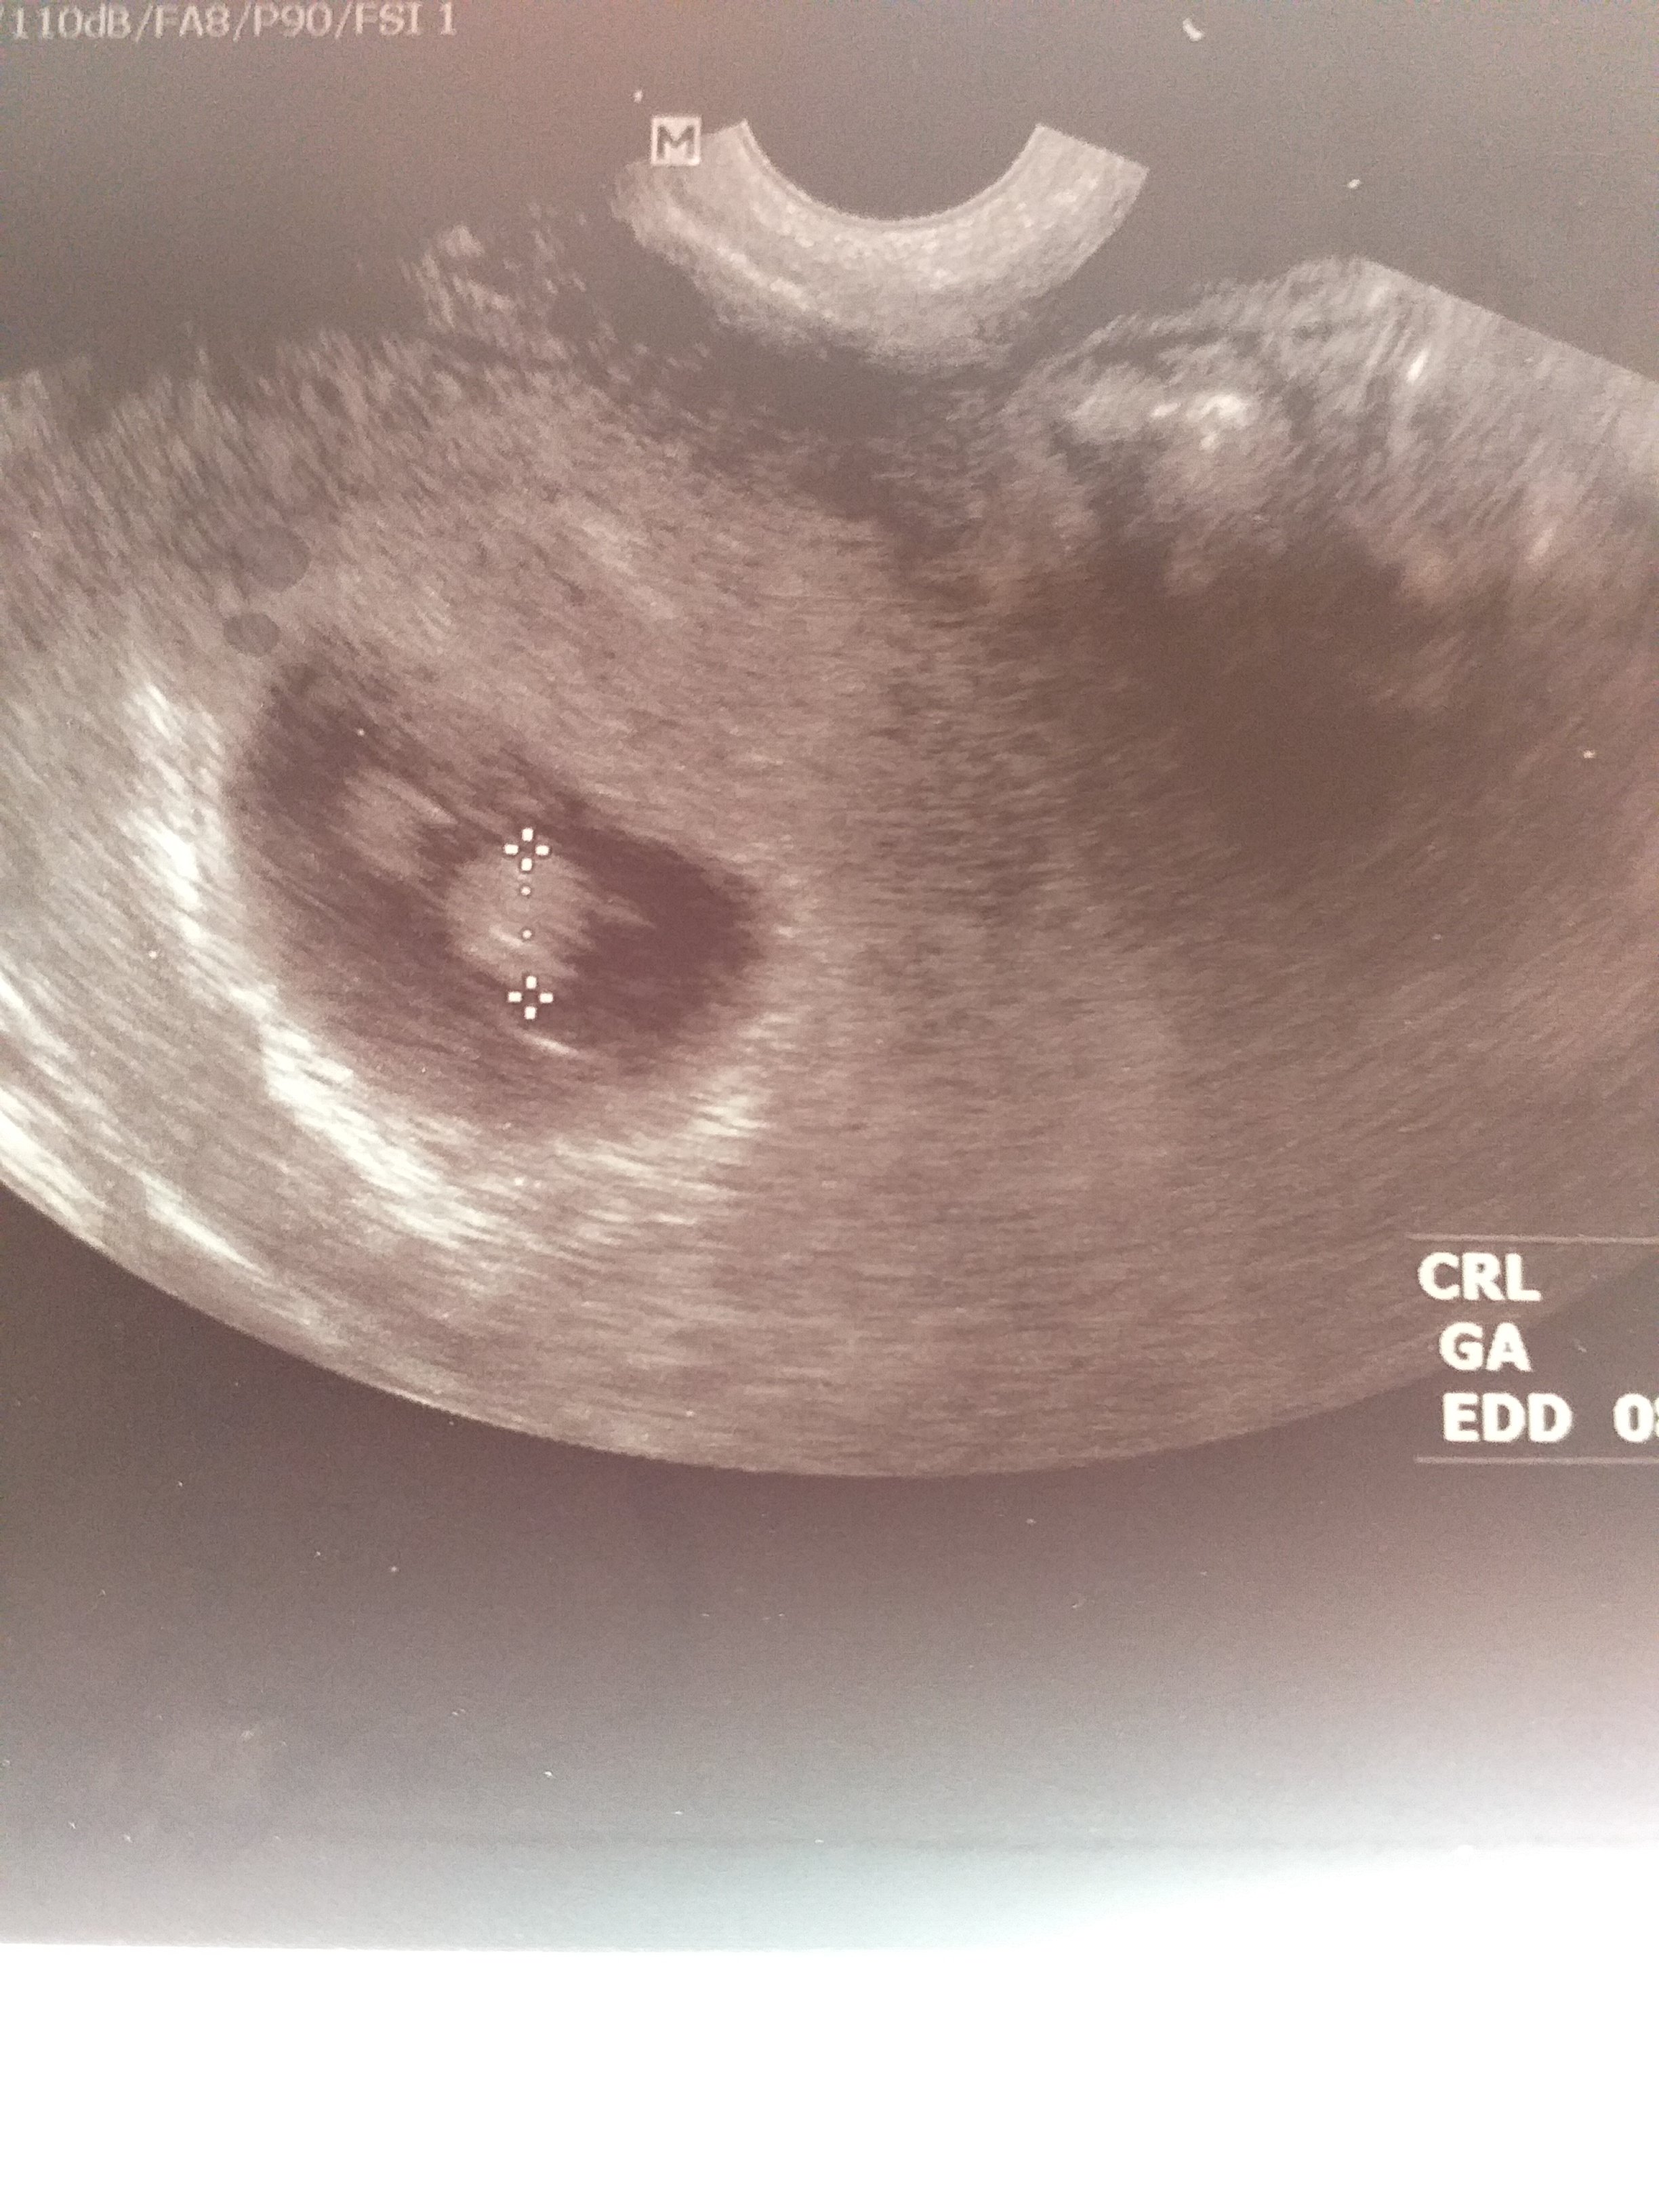

Mam pytanie najlepiej do mam bliźniąt, na zdjęciu usg widać jakby drugi płód. Jednak lekarz wpisał ciąża pojedyncza, zdjęcie usg z 7tygodnia +6dni. Dodam, że to moja druga ciąża lecz w czasie pandemii poszłam do pani ginekolog, która akurat miała termin i to co robiła było jakby z przymusu. Przechodząc do sedna, czy "to coś " widoczne w prawym górnym rogu to drugi płód? Jeśli nie to co to może być?